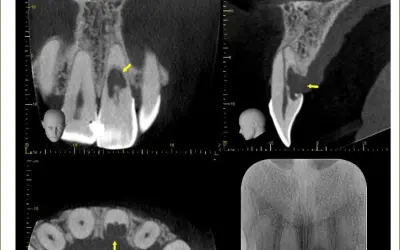

O desgaste de pinos estéticos cimentados é considerado um procedimento de alta complexidade, em razão do eminente risco de fragilização e perfuração radicular, sobretudo, a partir do uso de brocas de alta rotação. Destarte, recomenda-se que esse procedimento seja realizado com pontas ultrassônicas e “à luz da microscopia operatória”.

Por meio da radiografia inicial, deve-se identificar o tipo e as características do retentor (serrilhado, cilíndrico, liso, cônico, com ou sem fio-guia etc.). Geralmente, as cores do pino e da dentina são distintas, o que contribui para que somente o pino seja desgastado, preservando as paredes radiculares. A presença de um fio-guia (fio metálico localizado no centro do pino em todo o seu comprimento) favorece à remoção sem desgastes excessivos nas paredes do canal.

6.O diâmetro das pontas de ultrassom deve ser compatível com o do canal em cada terço radicular. A realização de radiografias transoperatórias é fortemente recomendada.

8.Radiografia final.